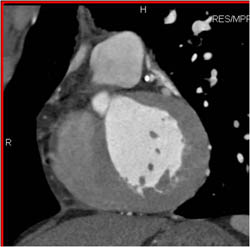

Plaque in LAD